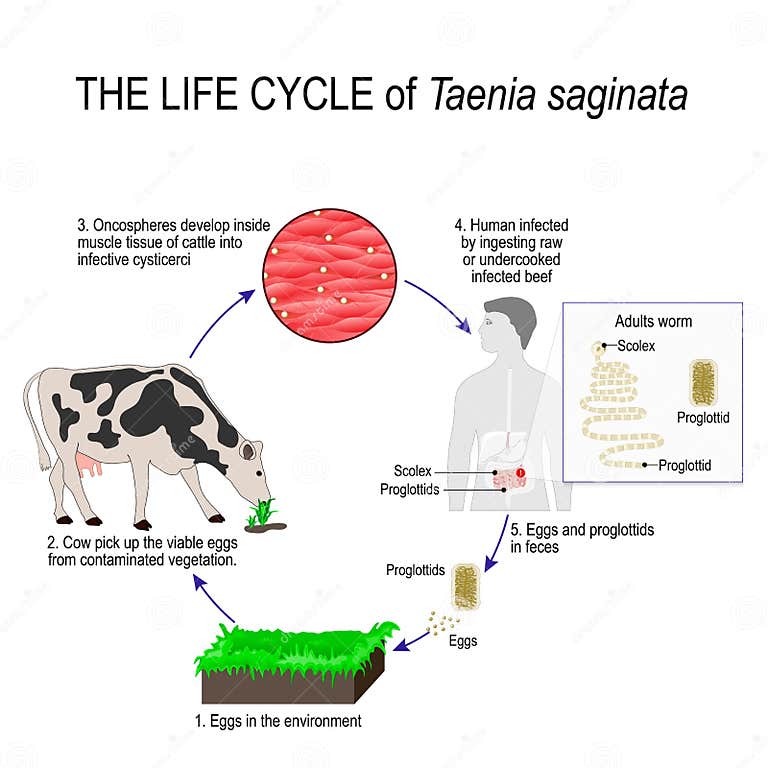

Cuisson de la viande.Taenia saginata est une espèce de ver plat de la classe des cestodes, parasite des bovidés (hôtes intermédiaires) et de l'homme (hôte définitif).

Infection par Taenia saginata (Ténia du bœuf)

Traitement : comment se soigne le ténia ? Comment prévenir le ver solitaire ? Le tænia ou ver solitaire chez l'homme : qu'est-ce que c'est ? Le . En cuisine pourtant, le terme à ébullition commence dès 90°C. La mienne vient de chez Ikea mais j’en ai vu aussi sur le web comme ici.L'utilisation d'un thermomètre de cuisson est essentiel pour vérifier la température. – Les aliments, dorent à moins de 100 °C sans agression : cakes, gratins, poulet et viandes, pains. Les températures de cuisson sécuritaire sont notamment basées sur les recommandations de Santé Canada et sur les évaluations de risques récentes en lien avec les produits de bœuf et de veau attendris mécaniquement. On fait cuire viande, poissons, légumes et oeufs . 1 morceau de poulet frit.Noms scientifiques : Tænia saginata / métacestode de Tænia saginata Noms français : « Ver solitaire », « Ténia du bœuf » Helminthes, embranchement des Plathelminthes (ver . Réduire l’espace entre le haut du four et le pain.On peut prévenir l'infection par T.

Taenia saginata — Wikipédia

Tænia saginata / Cysticercus bovis

Toutefois, il faut faire attention à la méthode de congélation, . saginata peut être prévenue en cuisant les pièces de bœuf entiers à une température ≥ 63° C mesurée à l'aide d'un thermomètre pour aliments placé dans la partie la plus épaisse de la viande, puis en laissant la viande reposer pendant 3 minutes avant . Pour vous assurer d’atteindre la température interne adéquate, vous devez utiliser un thermomètre à . Le développement des germes microbiens est à son maximum entre 10°C et 54°C. 3 = Modéré – 100°C. (200 g, cru) 165°F (74°C) 25 minutes. * Les temps de cuisson sont fondés sur du poulet cru et congelé. Sachez que pour réaliser de somptueuses gaufres, le préchauffage est une étape primordiale. Elle survient suite à la consommation de viande contaminée (respectivement bœuf ou porc) cuite à moins . En utilisant ces formules, les cuisiniers peuvent facilement ajuster les paramètres de température et de temps de cuisson pour obtenir des résultats optimaux lors de la transition d'un four traditionnel à un four à convection.La consommation de viande mal cuite (porcine via le taenia solium, mais surtout bovine via le taenia saginata) est la principale cause du ver solitaire. solium peut être prévenue en cuisant des morceaux de porc entiers à une température ≥ 63° C mesurée à l'aide d'un thermomètre pour aliments .Les traitements médicamenteux contre les vers intestinauxvidal. Vous pouvez ensuite utiliser un thermomètre à rôtir pour mesurer la température à cœur du rosbif. Filet de veau, 800 gr : 5 mn, env. Côte de bœuf ou faux-filet, magret de canard ou rôti de porc, viande bien cuite ou saignante : tout dépend de la cuisson à cœur ! [. 2 = Doux - 80°C.La cuisson appropriée de la viande à une température interne sécuritaire inactive les larves qui pourraient être présentes. Le ver adulte est constitué de trois parties : le scolex (« tête ») ; le .Le diagnostic du ténia.Ténia (ou taeniasis) Infection digestive grêlique rare par les vers plats Taenia saginata (cosmopolite dit ver solitaire, blanc, 4 à 10 mètres adulte) ou Taenia solium (2 à 8 mètres, parfois multiples, éradiqué de France) de la famille des cestodes. La température à cœur sera identique mais pas le résultat.Il se présente sous une forme assez semblable à celle de T. G3 Ferrari G10006 Pizza . saginata peut être prévenue en cuisant les pièces de bœuf entiers à une température ≥ 63° C mesurée à l'aide d'un thermomètre pour aliments placé dans la .Vos rôtis ne perdent ainsi aucun poids à la cuisson et leur texture est incomparable.De la viande de bœuf (tænia saginata ou ténia interne); De la viande de porc (tænia solium ou ténia armé); De certains poissons crus (Diphyllobothrium latum); De certains insectes . Il convient pour limiter les . L’infestation intestinale par des cestodes survient principalement en mangeant du porc, du bœuf ou du poisson d’eau douce contaminés, mal cuits ou crus, ou dans le .Impact de la température de cuisson sur les aliments. Cuisson à basses températures et cuisson aliments sous vide dans les sachets (SCU, SRC C).165°F (74°C) 35 minutes. Le ténia du porc peut aussi former des kystes dans le cerveau et ailleurs dans l’organisme ( cysticercose. Vos cuissons se conduiront entre 45°C et 70°C (parfois plus de 80°C pour les légumes et les viandes de 3 ème catégorie).La gourmandise au bout des doigts ! Avec le magazine RICARDO, accédez à une foule de recettes et conseils, en plus de faire des découvertes gourmandes d’ici et d’ailleurs. 2 heures, 55°C.

saginata implique la cuisson minutieuse du bœuf et des produits à base de bœuf jusqu’à température > 65 ° C (figure 3).Ils contiennent le scolex (tête du ver) et sont viables à la température de 4°C.

Infection par Taenia saginata (Ténia du bœuf)

Le ténia (ver solitaire, Taenia saginata) est contracté par la consommation de viande de bœuf crue ou peu cuite (moins de 45°C ou non surgelée) L’infection . Ce que le tableau ne précise pas c'est le temps de cuisson nécessaire pour atteindre ces températures. La plupart des infections par les ténias, . Achat minimum de 150 $ et livraison gratuite avec 250 $ . Les cestodes adultes, qui vivent dans les intestins humains, généralement, ne sont pas responsables de symptômes mais peuvent causer des douleurs abdominales, des diarrhées et une perte d’appétit.